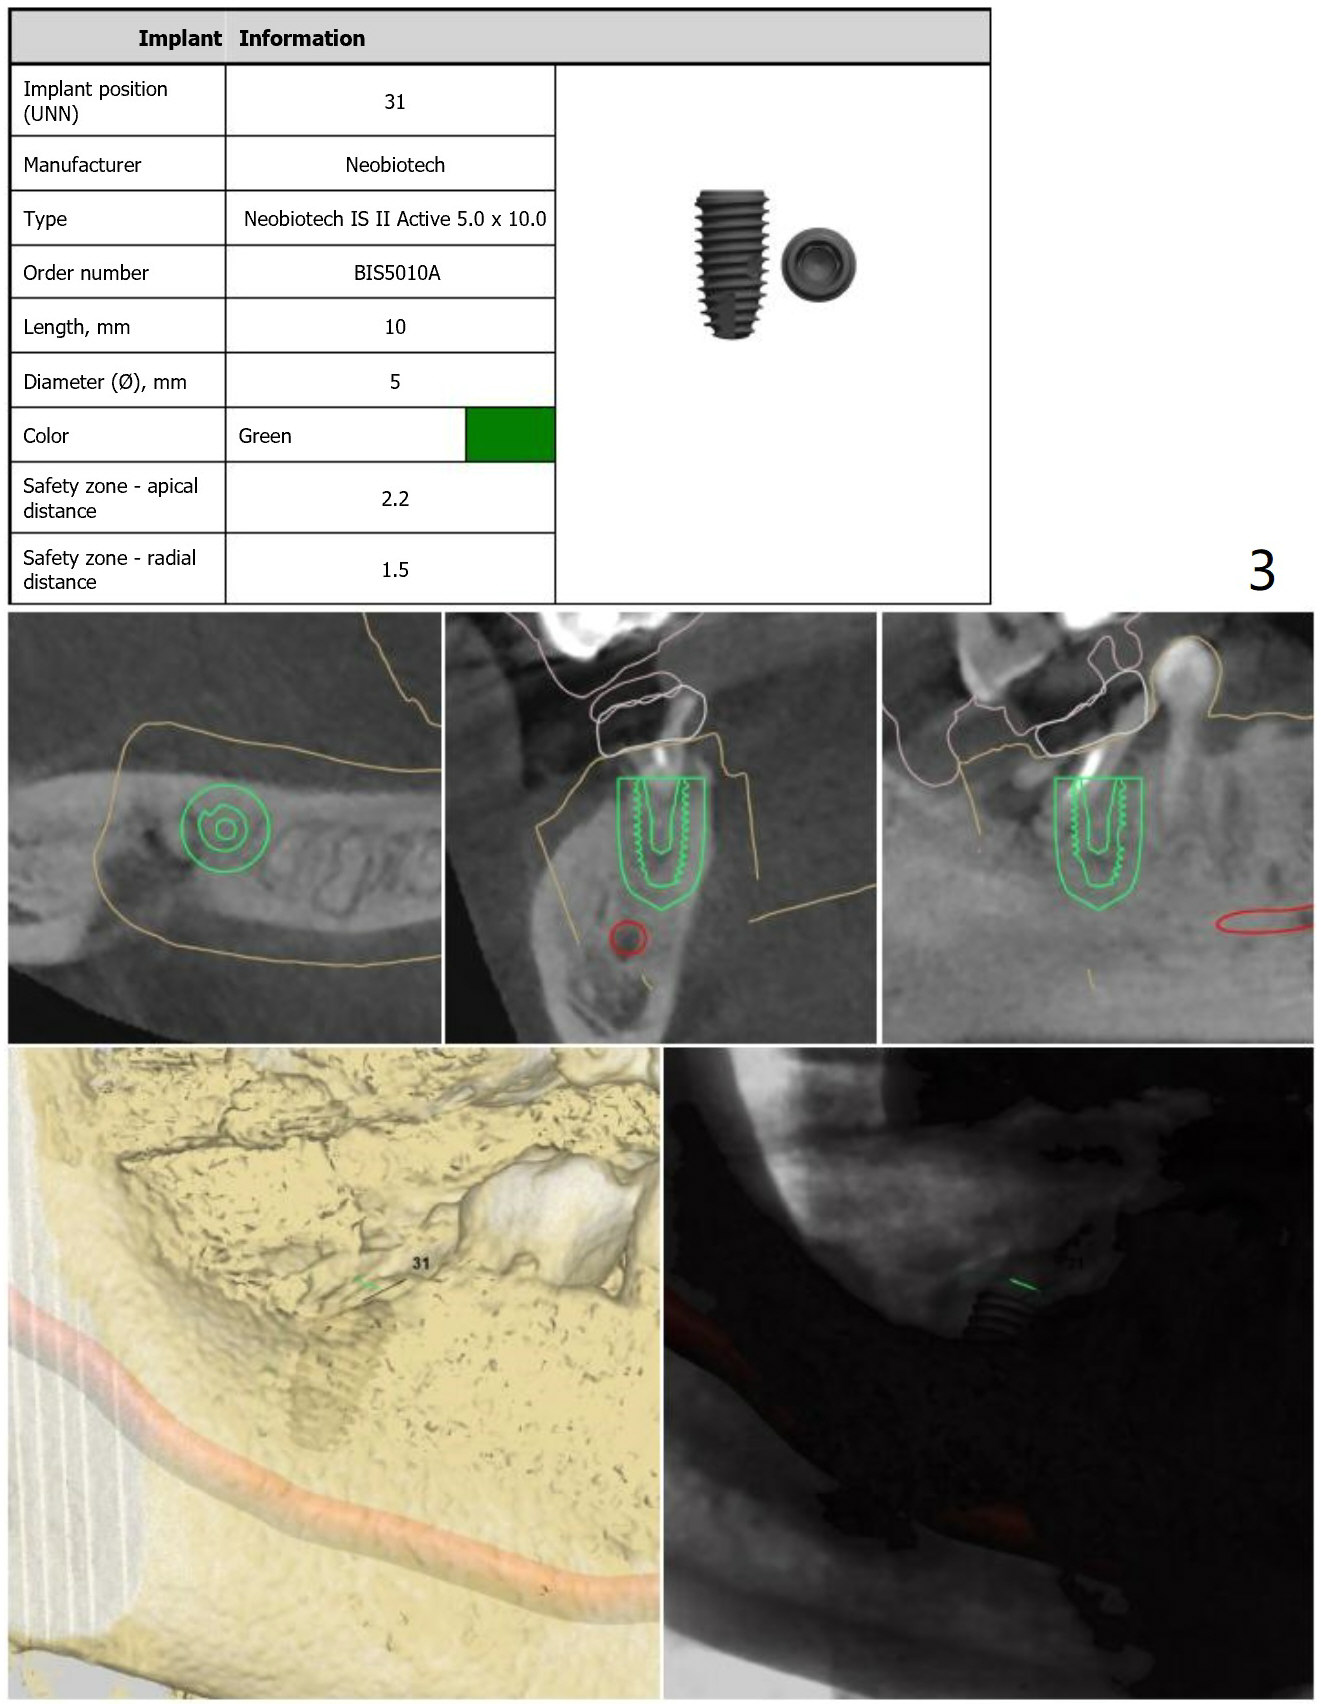

Dense Bone

A 56-year-old man agrees to have immediate implant at #31 (Fig.1-5) 2 year post (re)cementation at #14,15. Osteotomy should be gentle with copious irrigation because of dense bone (Fig.4). After implant osteointegration, a provisional will be fabricated to intrude the supraerupted tooth #2 (Fig.5).